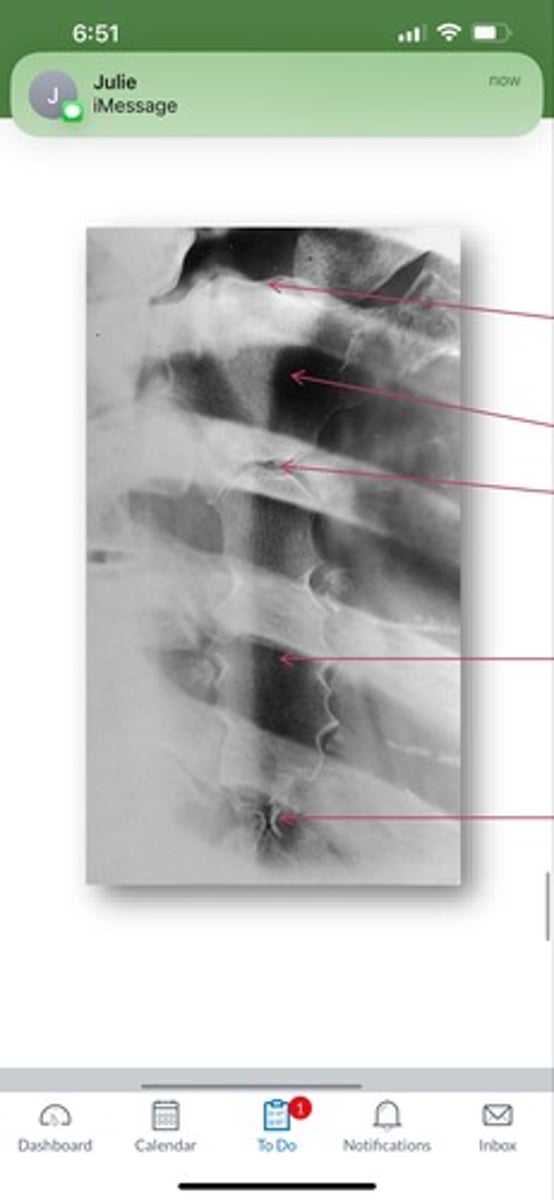

L5 R transverse process

A.

L4 Lower lateral portion

B.

L4 spinous process

C.

L3 R inferior articular process

D.

L4 L superior articular process

E.

L1-2 intervertebral disk space

F.

AP Lumbar

What position?